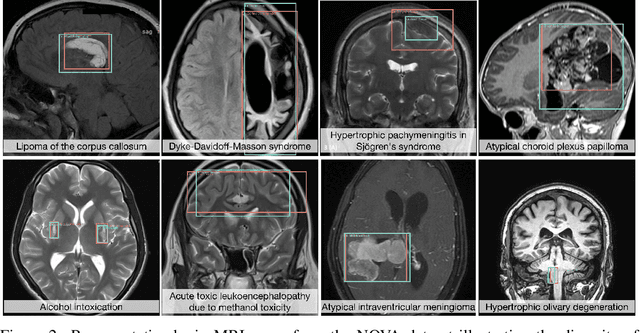

Abstract:In many real-world applications, deployed models encounter inputs that differ from the data seen during training. Out-of-distribution detection identifies whether an input stems from an unseen distribution, while open-world recognition flags such inputs to ensure the system remains robust as ever-emerging, previously $unknown$ categories appear and must be addressed without retraining. Foundation and vision-language models are pre-trained on large and diverse datasets with the expectation of broad generalization across domains, including medical imaging. However, benchmarking these models on test sets with only a few common outlier types silently collapses the evaluation back to a closed-set problem, masking failures on rare or truly novel conditions encountered in clinical use. We therefore present $NOVA$, a challenging, real-life $evaluation-only$ benchmark of $\sim$900 brain MRI scans that span 281 rare pathologies and heterogeneous acquisition protocols. Each case includes rich clinical narratives and double-blinded expert bounding-box annotations. Together, these enable joint assessment of anomaly localisation, visual captioning, and diagnostic reasoning. Because NOVA is never used for training, it serves as an $extreme$ stress-test of out-of-distribution generalisation: models must bridge a distribution gap both in sample appearance and in semantic space. Baseline results with leading vision-language models (GPT-4o, Gemini 2.0 Flash, and Qwen2.5-VL-72B) reveal substantial performance drops across all tasks, establishing NOVA as a rigorous testbed for advancing models that can detect, localize, and reason about truly unknown anomalies.